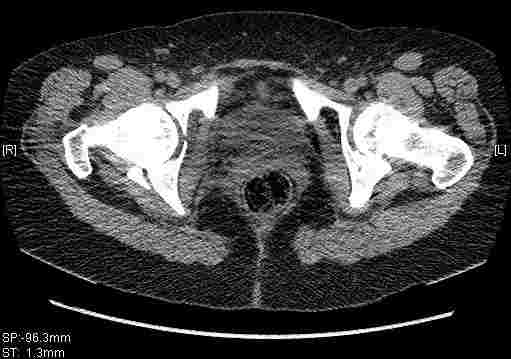

Женщина,58 лет, после ДТП 6 суток. Первично повреждение расценено как переломы ветвей лонной кости. После подтверждения повреждения вертлужной впадины,как чаще всего случается, вопрос встал о тактике. БОльшинство за консерватиное лечение.К сожалению кт у нас "во время" сломался. Прилагаю стандартные снимки вертлужки. У меня следующие вопросы к коллегам:1. Правильно ли рассценивать это повреждение как Т-образный перелом вертлужнй впадины?2. Можно ли добиться анатомической репозиции поверхности вертлужной впадины скелетным вытяжением в данном случае, если нет, что будет этому препятствовать?3. Если смещение останется таким как сейчас, через какое время появится необходимость эндопротезирования (по вашему опыту)?Спасибо.

Удалось сегодня вывести пациентку в соседнюю больницу, где есть кт. Срезы сделаны только горизонтальные.

Следом 3d